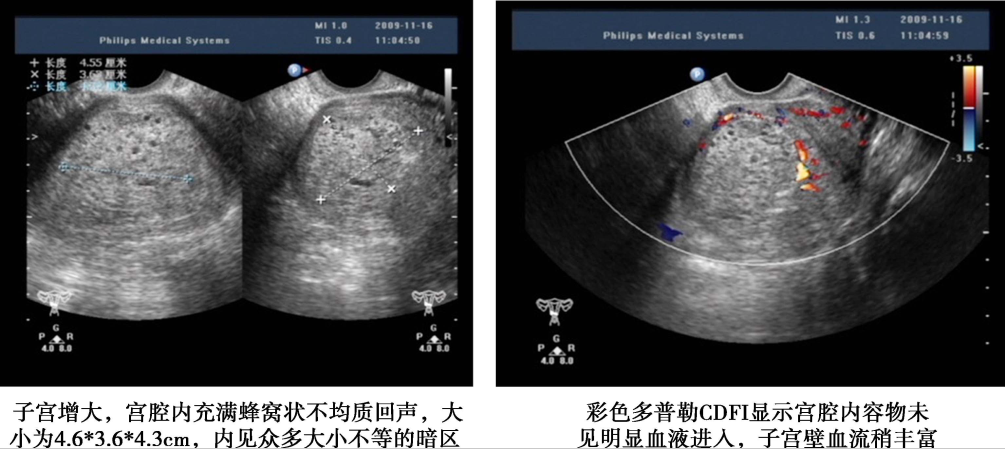

1.超声检查 是常用的辅助检查,最好采用经阴道彩色多普勒超声。完全性葡萄胎的典型超声图像为子官大于相应孕周,无妊娠囊或胎心搏动,宫腔内充满不均质密集状或短条状回声,呈“落雪状”,水泡较大时则呈“蜂窝状”。常可测到双側或一侧卵巢囊肿。彩色多普勒超声检查可见子宫动脉血流丰富,但子宫肌层内无血流或仅稀疏血流信号。部分性葡萄胎可在胎盘部位出现由局灶性水泡状胎块引起的超声图像改变,有时还可见胎儿或羊膜腔,胎儿通常畸形。早期葡萄胎妊娠的超声征象常不典型,容易误诊。

完全性葡萄胎超声影像(患者A)

子宫增大,宫腔内充满蜂窝状不均质回声,大小7.5cm×6.3cm×5.3cm,内见众多大小不等暗区